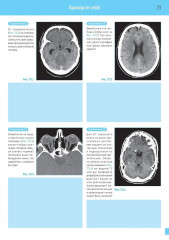

💳 Оплатить за товар можно при получении 🇰🇿 Есть бесплатная доставка по Казахстану от 1 дня 🎁 Копите бонусы с каждой покупки Четвертое издание на русском языке представляет собой базовый курс подготовки и переподготовки специалистов по компьютерной томографии по международным стандартам. Представлен систематизированный подход к анализу компьютерных томограмм всех частей тела. Описаны самые современные методики, включая КТ-ангиографию, КТ с двумя источниками и ПЭТ/КТ. Книга содержит более 1000 высококачественных иллюстраций — компьютерных томограмм со схемами, иллюстрирующими их анатомический смысл и диагностическое значение. Каждая глава содержит задания для самоконтроля, что позволяет читателю самостоятельно организовать и контролировать процесс обучения. |